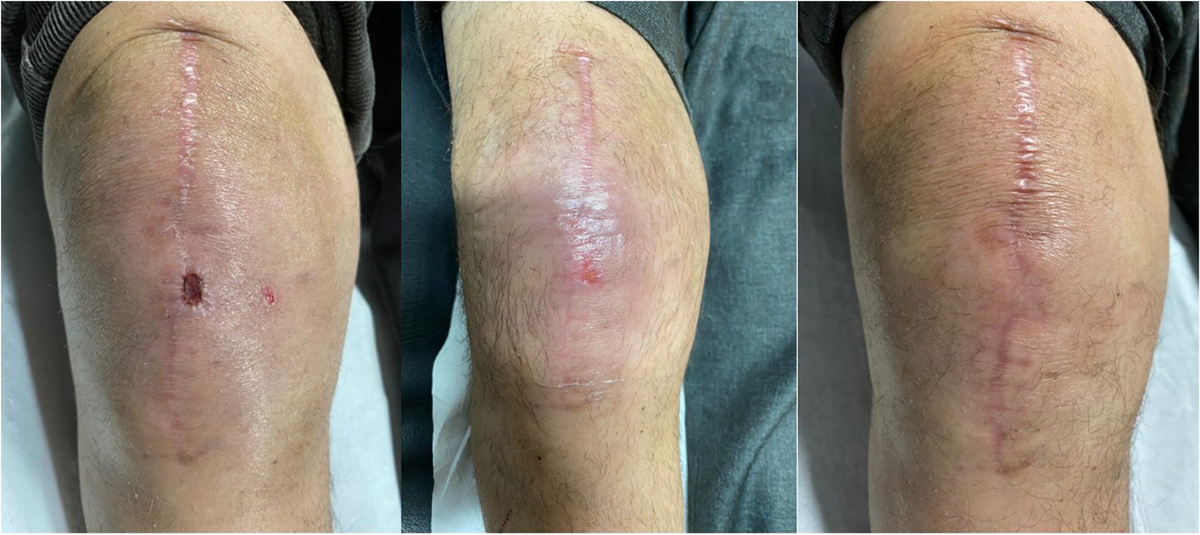

Post-surgical non-healing wounds

Post-surgical non-healing wounds

Sometimes after surgery, the wound does not heal as expected — this is known as a post-surgical non-healing wound.

Such wounds occur when the body’s normal healing process is delayed due to infection, poor blood circulation, weak immunity, or underlying health conditions.